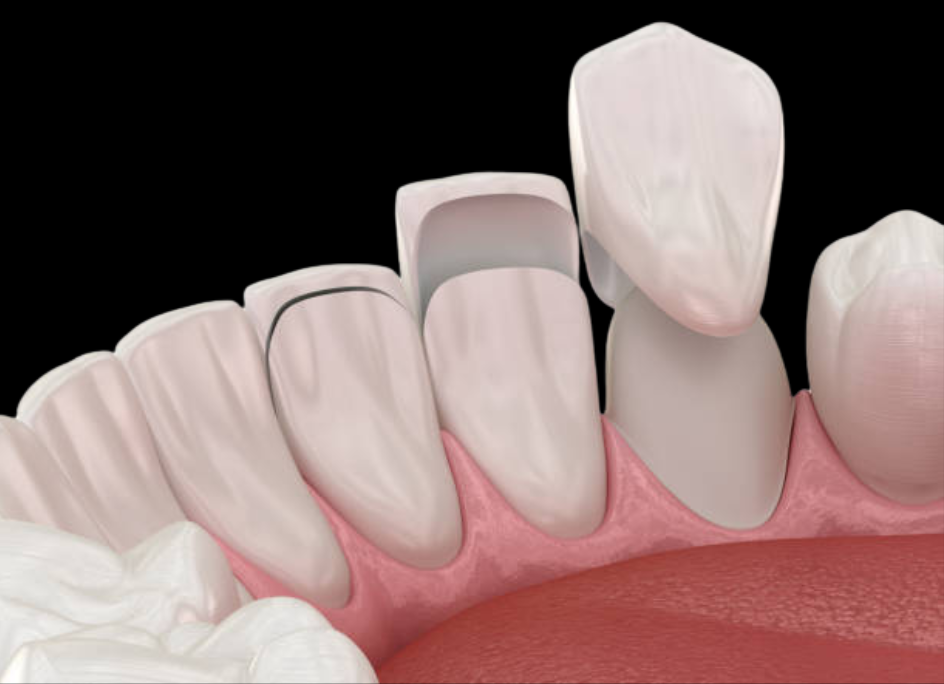

- Coronas y carillas dentales: Perfectos para corregir imperfecciones estéticas y funcionales.

Diseño de sonrisa

Este tratamiento combina estética dental avanzada para transformar tu sonrisa de forma personalizada. Incluye procedimientos como:

- Carillas dentales.